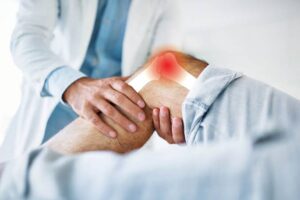

At Rajkala’s Physio plus clinic, we support our patients to get more out of life today. Our mission is to provide the highest quality, hands-on, dynamic Physiotherapy to allow patients to recover and fulfil individual goals. We pride ourselves as a ‘Hands-on’ 1:1 approach to treatment ensuring you get the best results.

At Rajkala’s, we take an unique and innovative approach. Using a variety of techniques and therapy equipments, our experienced physiotherapists assess your symptoms and deliver more effective treatments for your pain.

At Rajkala’s Physiotherapy Centre, we don’t see you as just another patient. We understand that your body and your circumstances are highly unique, which is why we provide distinctive treatment to each client that will most benefit the individual. We want your treatment experience to be positive and effective.

At Rajkala’s Sports Physiotherapy, we offer a wide range of physiotherapy services to help with back and neck pain, sports injuries, post-operative rehabilitation, trapped nerve conditions, joints, ligaments and muscular injuries and various work or sporting-based assessments.

Musculoskeletal Physiotherapy

Restriction of bodily movement can be quite a frustrating experience, particularly if you don’t understand the cause of the pain. Our experienced musculoskeletal physiotherapists can help put your mind at ease and assist in finding the right treatment plan to improve your overall bodily movement and function.